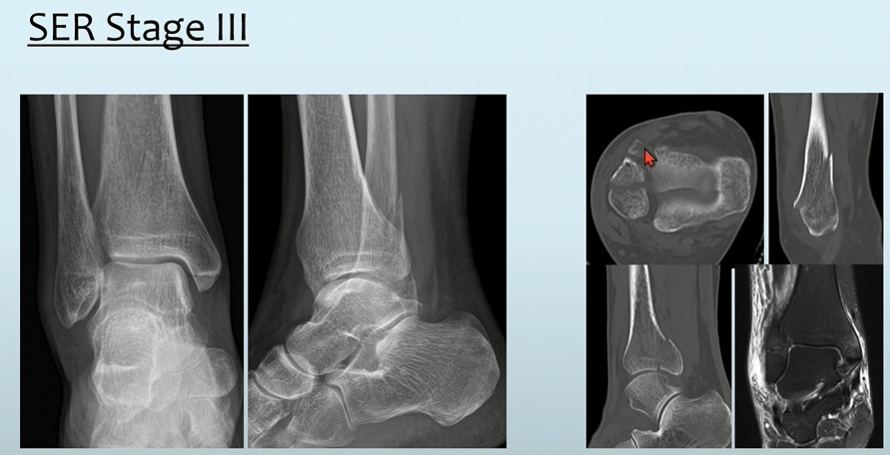

Stage2에 합당한 소견이 보이면서, PM 골절이 동반되어 stage 3라고 판단할 수 있습니다.